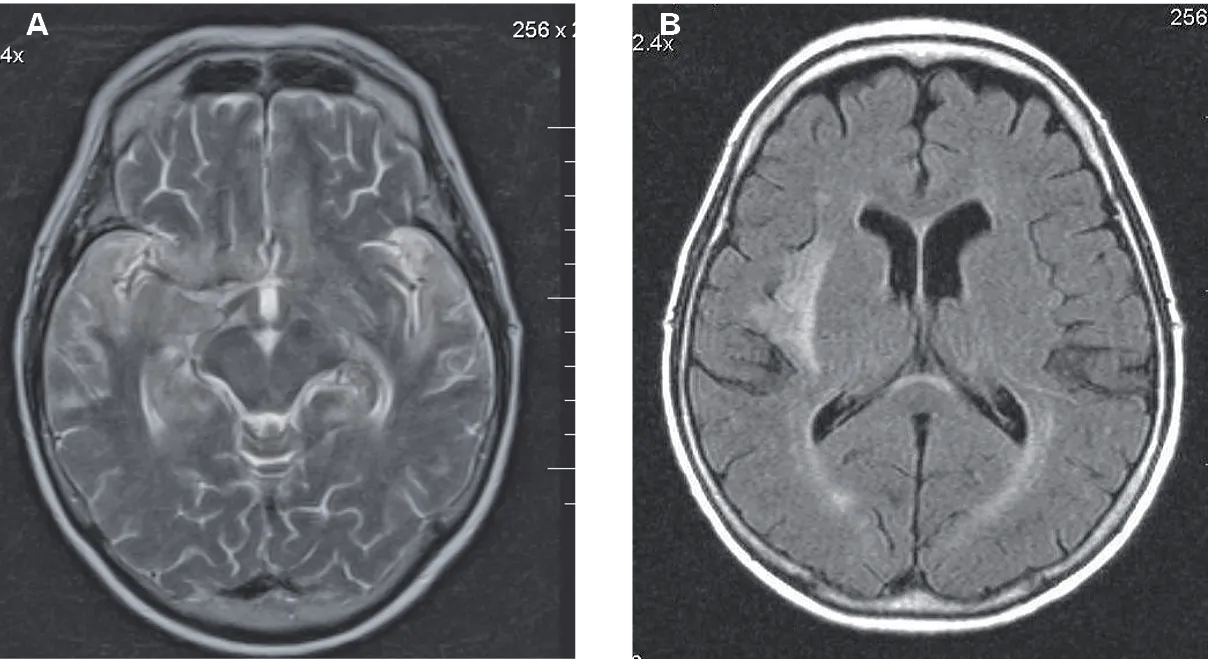

Konsultacja z neurologiem jest kluczowa do oceny fizycznych uszkodzeń mózgu. Neurolog może zlecić badania takie jak rezonans magnetyczny (MRI) lub tomografia komputerowa (CT), aby zobrazować strukturę mózgu i wykryć ewentualne zmiany. Psychiatra natomiast zajmuje się diagnozowaniem i leczeniem zaburzeń psychicznych, które często towarzyszą uzależnieniu od dopalaczy, takich jak depresja, lęki czy psychozy. W leczeniu mogą być pomocne leki nootropowe, które poprawiają funkcje poznawcze, leki antydepresyjne, przeciwlękowe, a w niektórych przypadkach nawet neuroleptyki, jeśli występują objawy psychotyczne. Ważne jest, aby wszelkie leczenie farmakologiczne odbywało się pod ścisłym nadzorem lekarza.